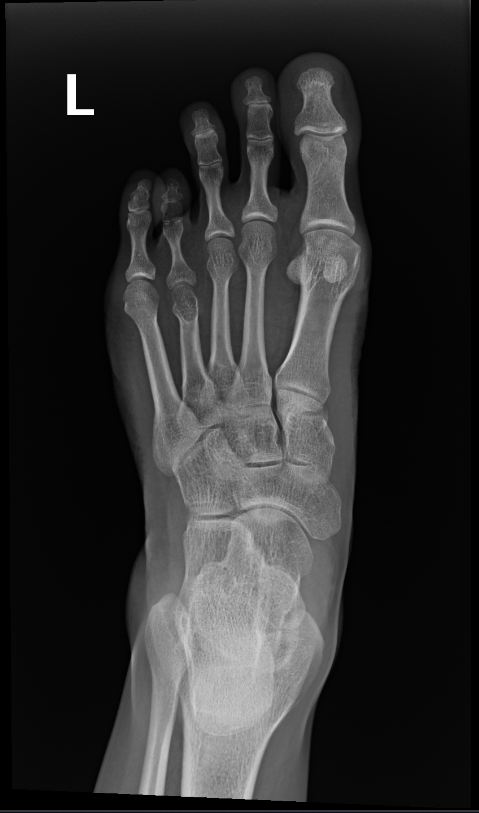

The surgeon in preparation for each surgery preconstructs a customized apparatus. Using wires or pins, the apparatus is surgically attached to the affected limb. Surgery is usually performed percutaneously through small incisions. Special care is taken to minimize injury to the bone and surrounding soft tissue, nerves and blood vessels when making specialized bone cuts.

After the desired length has been achieved and the limb has been straightened, no further adjustments are made. The apparatus is left in place to allow the new bone to harden and mature. Once the new bone is judged to be sufficiently strong, the frame is removed under a short general anesthetic. A cast or brace may be applied for an additional month or two for further protection. The new bone tissue assumes all the qualities and strength of normal bone with time.